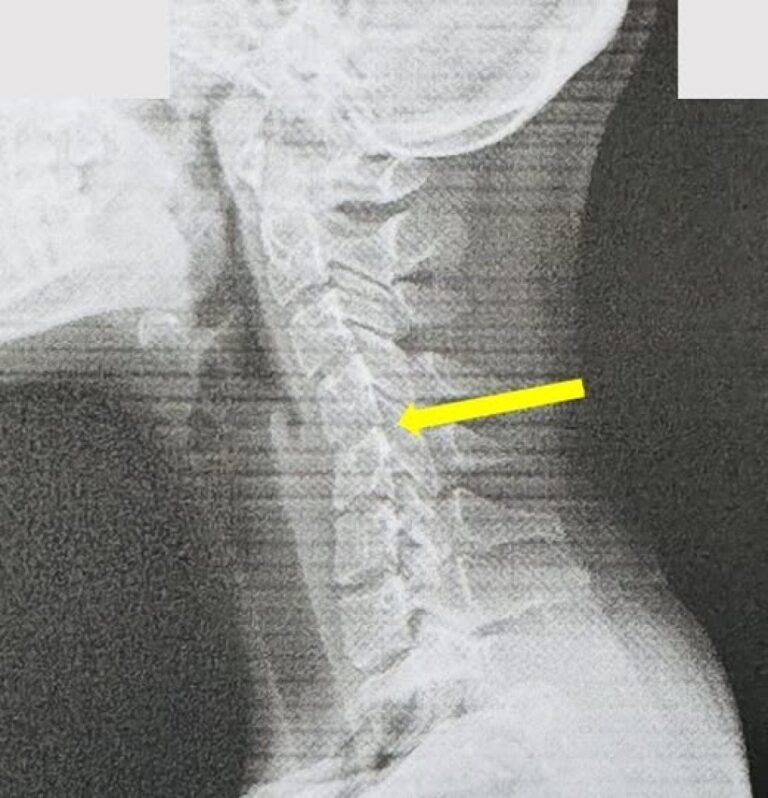

圖說:員榮葉宗勳醫師解釋 一般低頭族滑手…